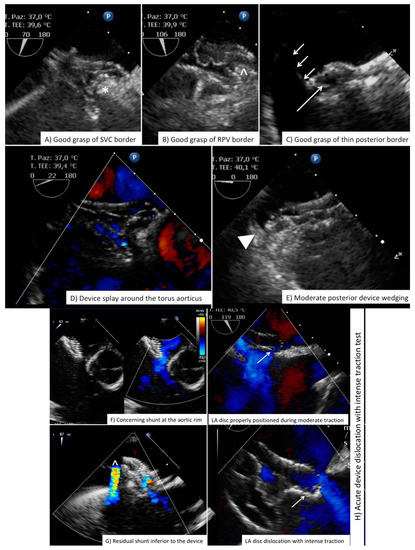

| Before vascular access | Free LA appendage Normal aortic and mitral valve No intracardiac mass Atrial septal aneurysm Eustachian valve Chiari Network Accessory fenestration Antero-posterior septal distance | Free LA appendage No significant mitral valve disease Atrial septal aneurysm Eustachian valve Chiari Network Assess border features Multifenestrated ASD Confirm normal pulmonary vein anatomy Bidimensional and color-based shortest and largest ASD diameter 3D-based shortest and largest ASD diameter |

| After vascular access | Confirm right-to-left shunt at intracardiac bubble study Confirm correct tunnel wiring Confirm wire position in the proper pulmonary vein PFO tunnel amplitude and length | Confirm wire position in the proper pulmonary vein Balloon sizing in stop-flow condition |